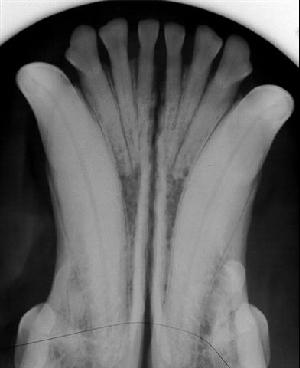

Due to where the tumor was/will be when it comes back (next to his mandibular symphysis), the surgery will be more involved than normal. The mandible is comprised of two halves joined together on the midline at the mandibular symphysis, which is a fibrocartilaginous joint aka his bottom jaw is actually two bones that come together at the front of his mouth (note the gap shown in this random, not Monty’s mouth xray – if it was Monty, those six little teeth would all be gone!). So surgery needs to be very careful in this area since it’s not just regular bone and involves a joint.